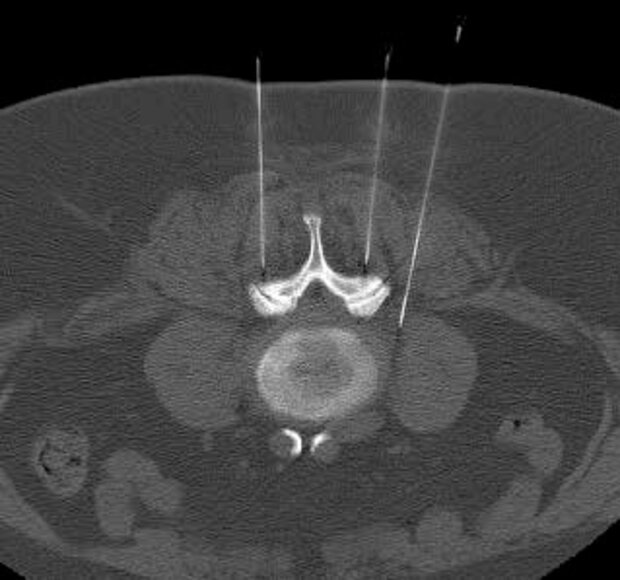

Anschließend wird die eigentliche Behandlungsnadel im genau vorgeplanten Winkel, in der richtigen Höhe der Wirbelsäule millimetergenau bis an Nervenwurzel und das Wirbelgelenk vorgeschoben. Dies ist nahezu schmerzfrei – man spürt „einen Druck“ im Rücken. Das anschließend angefertigte Kontroll-CT-Schnittbild zeigt eine korrekte Lage der Behandlungsnadel. Erst jetzt wird das Medikament exakt positioniert.

• Millimetergenaue Positionierung der Nadel und des Medikamentes.

• Dadurch hohe Wirkstoffkonzentration am Schädigungsort der Wirbelsäule und eine hohe Sicherheit zur Vermeidung von Nerven- und Gefäßverletzungen. Die beschriebene Intervention dauert ca. 10 Minuten.